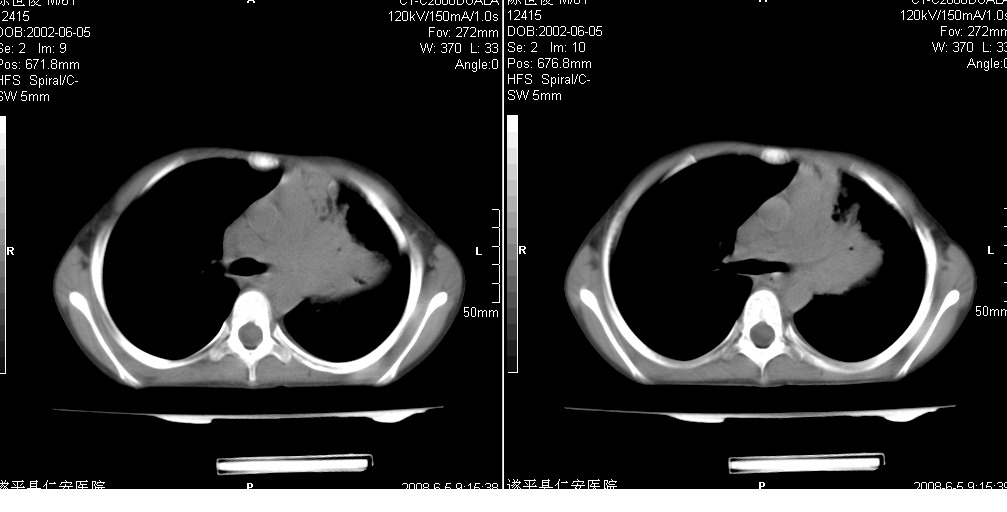

以下是引用xxhwh在2008-6-10 18:40:00的发言:[br]男,6岁,无规则发热一月余,体温在37.8——39度之间。一月前拍胸片示左上肺密度增高影,进行抗炎治疗8天,复查胸片未明显吸收。又改变抗菌素继续治疗半月,照胸片示病灶吸收不明显,行ct检查[br]征象:左上肺前段呈密实影,内可见支气管气像,远侧见絮状模糊影,中上纵隔左移。[br]意见:左上肺前段膨胀不全及感染,考虑为支气管异物或支气管内膜结核所致,[br]建议追问有无异物吸入史,行痰检及ppd检查